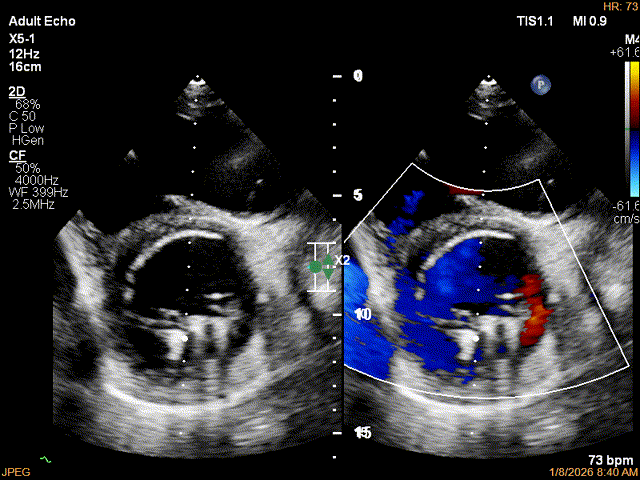

彩色多普勒显示反流明显减少

第二枚XTR植入后瓣口平均压差3mmHg

第3枚XTR夹合器植入后,跨瓣平均压差为3mmHg

最终结果3D-Zoom-color显示组织桥稳定,原脱垂区域前后叶对合部分的脱垂已消除,反流降至1+以下

夹子释放Bi-com切面显示残余反流情况

肺静脉收缩期逆流消失,频谱形态基本恢复正常

术后2D TTE:

术后TTE可见二尖瓣微量-轻度反流,三尖瓣反流明显改善降至中度